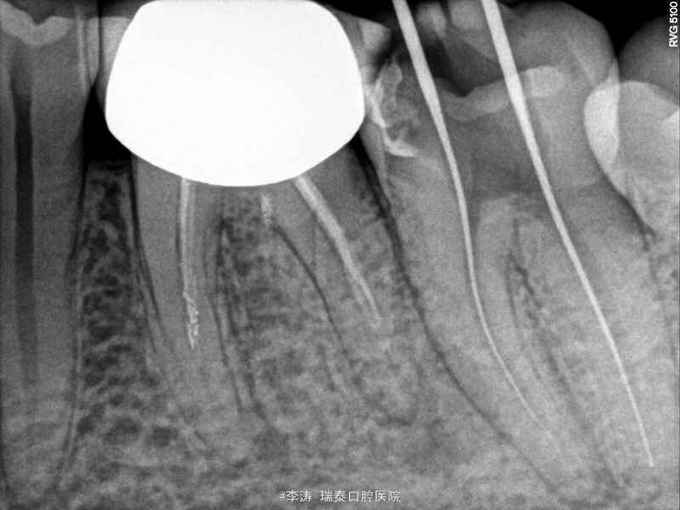

37牙去龋未净时穿髓 行根管治疗,开髓,根管预备,但根管预备封药后两天开始疼痛,叩痛明显,去除封药,未见明显分泌物,根管荡洗干燥后重新封药,但症状一直持续,自服止疼药后缓解,两周以后疼痛消失予以根充

根管封药后疼痛的原因?药物导致的根尖周炎?合创伤?预备时器械超出根尖孔导致的组织损伤?细菌感染? 怎样才能做到每次就诊封药后不疼?这真是一个值得考虑的问题